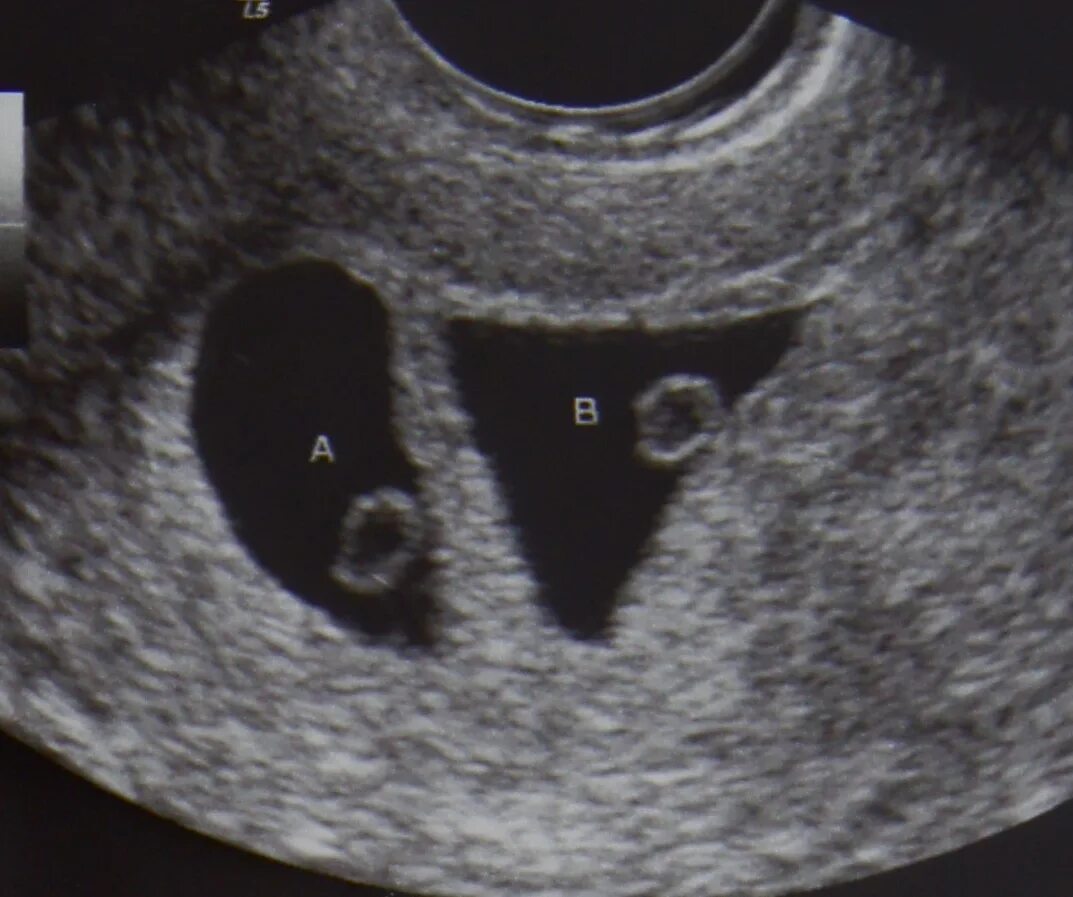

Плодное яйцо 3 мм